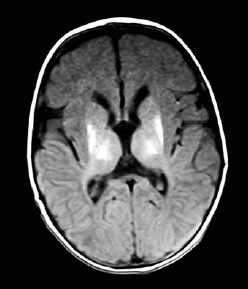

Paciente com atraso global do desenvolvimento, ataxia e apraxia oculomotora apresenta o achado de imagem a seguir.

O diagnóstico é